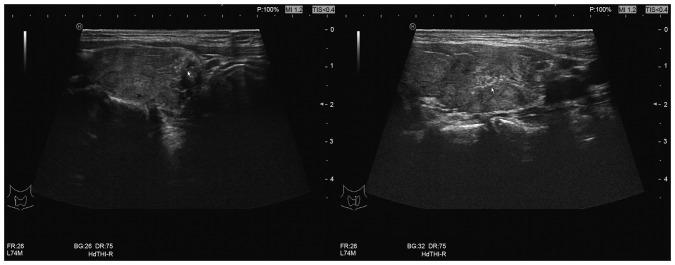

Resistance to thyroid hormone (RTH) is a rare autosomal hereditary disorder characterized by increased serum thyroid hormone (TH) levels with unsuppressed or increased thyrotropin concentration. It remains unknown whether the coexistence of RTH with papillary thyroid carcinoma (PTC) and Hashimoto thyroiditis (HT) is incidental or whether it possesses a genetic or pathophysiological association. In the present study, a case of RTH with PTC and HT in an 11-year-old Chinese patient was examined and the clinical presentation of RTH with PTC was discussed. In addition, the possible associations between RTH, PTC and HT were determined. HT was confirmed in the patient using an autoimmune assay and thyroid ultrasound. RTH was diagnosed on the basis of clinical manifestations, laboratory information and gene analysis, and PTC was diagnosed according to histological results. Results of BRAF mutation analysis were positive. A literature review of 14 cases of RTH with PTC was included for comparison. The present case report indicates an association of RTH with PTC and HT coexistence in the patient. Close follow-up, histological evaluation and BRAF mutation detection should be performed in each RTH case with HT, since a persistent increase in TSH may be a risk factor for the development of thyroid neoplasm.

甲状腺激素抵抗(RTH)是一种罕见的常染色体遗传性疾病,其特征是血清甲状腺激素(TH)水平升高,同时促甲状腺素浓度未被抑制或升高。RTH与甲状腺乳头状癌(PTC)和桥本甲状腺炎(HT)并存是偶然现象,还是存在遗传或病理生理关联,目前尚不清楚。在本研究中,对一名11岁中国患者的RTH合并PTC和HT病例进行了检查,并讨论了RTH合并PTC的临床表现。此外,还确定了RTH、PTC和HT之间可能的关联。通过自身免疫检测和甲状腺超声检查确诊该患者患有HT。根据临床表现、实验室检查信息和基因分析诊断为RTH,根据组织学结果诊断为PTC。BRAF突变分析结果为阳性。纳入14例RTH合并PTC病例的文献综述进行比较。本病例报告表明该患者中RTH与PTC和HT并存有关联。对于每例合并HT的RTH病例,均应进行密切随访、组织学评估和BRAF突变检测,因为促甲状腺素持续升高可能是甲状腺肿瘤发生的危险因素。